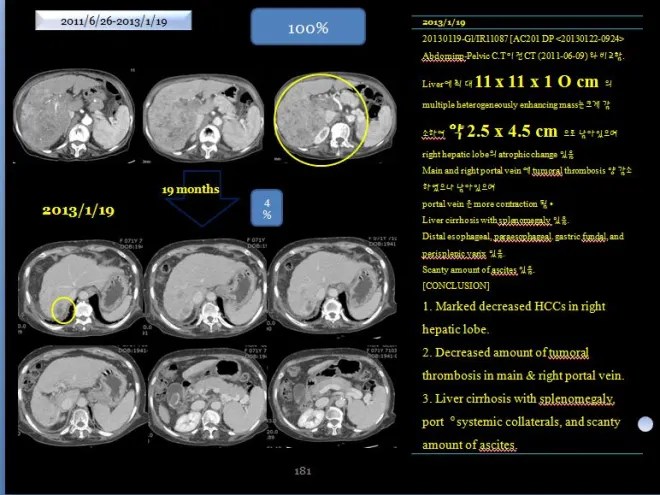

2) 2013년 1월 19 CT liver 19mo

사진에서 보듯이 간은 위축이 되었지만 커다란 종양은 거의 없어져서 일부분만 남아 있다. 당시 의무기록을 보면,

Abdominp-Pelvic C.T 이전 CT (2011-06-09)와 비교함.

Liver에 최대 11 x 11 x 10cm의 multiple heterogeneously enhancing mass는 크게 감소하여 약 2.5 x 4.5 cm 으로 남아 있으며 right hepatic lobe의 atrophic change 있음.

Main and right portal vein에 tumoral thrombosis 양 감소하였으나 남아 있으며

portal vein은 more contraction 됨.

Liver cirrhosis with splenomegaly 있음.

Distal esophageal, paraesophageal, gastric fundal, and perisplenic varix 있음.

Scanty amount of ascites 있음.

[CONCLUSION]

Marked decreased HCCs in right hepatic lobe

Decreased amount of tumoral thrombosis in main & right portal vein

Liver cirrhosis with splenomegaly, port。systemic collaterals, and scanty

amount of ascites

“2011년 년 6월 9일과 2013년 1월 19일 CT 를 비교함. 간에 있던 최대 장경 11x11x10cm의 균일하지 않케 조영되는 암은 크게 감소하여서 2.5x 4.5로 줄어들었다. 우측간은 위축되어 있고, main과 우측의 portal vein의 종양에 의한 thrombosis 양이 줄어들었으나 남아 있고, portal vein (문맥)은 더욱 수축되어 있다. 간경화와 비장종대도 있다. 식도와 위장 부근의 비장 옆의 정맥류가 보이며 약간의 복수가 있다.”

18 개월만에 간의 종양이 거의 체적대비하여서 4% 정도로 줄어들었고 2014 년도 3월에 통합의학대회에서 본인이 강의하기 전에 환자에게 CT 를 찍어볼 것을 권유하였다.